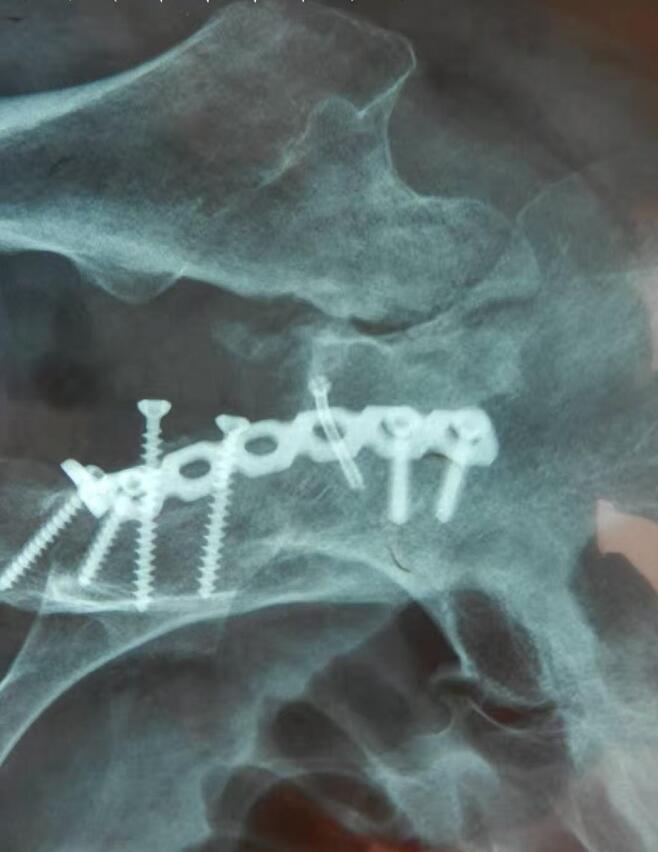

1995年8月,金华市区个体户赵连辉(男,38岁),因交通肇事外伤致颈椎椎骨骨折,颈椎椎间盘突出,压迫颈髓和相应神经根、椎管狭窄。医院治疗两个月后。只能依赖颈托外固定来支撑头部对颈部的压力。仍感颈部活动障碍,常感颈项部、双上肢、头部胀痛,睡眠不佳,不能干活,配服张小贵的中草药和药酒一个月后解除颈托,两个月后,上述症状自然消失,颈部和双上肢活动自如,照常刻章(系干低头手工精细活)干活至今。